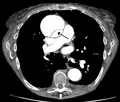

![]() |

| الأشعة المقطعية بالكمبيوتر (CT) | الصورة الرمزية |

| تسلخ الأبهر لحالة تنتمي للمجموعة A في تصنيف Stanford 1 الأبهر الصاعد، التجويف الشرياني الأصلي - 2 التجويف الشرياني الكاذب - 3 الشريان الرئوي 4 الأبهر الهابط - 5 فقرة صدرية | |

يعد تصوير الأوعية الدموية بالأشعة المقطعية بالكمبيوتر من الاختبارات السريعة غير الجراحية التي من شأنها توفير صورة دقيقة ثلاثية الأبعاد للأبهر. يتم التقاط هذه الصور عن طريق أخذ صور مجزأة رقيقة وسريعة للصدر والبطن، والجمع بينها باستخدام الكمبيوتر لتكوين شرائح مستعرضة. لتصوير الأبهر بالدقة اللازمة للوصول إلى التشخيص السليم، يتم حقن مادة تباين معالجة باليود في أحد الأوردة المحيطية (الطرفية). تُحقن مادة التباين وتُجرى الأشعة باستخدام تقنية تتبع الدفقة (Bolus Tracking method). يعد هذا نوعًا من الأشعة المتزامنة مع الحقن بهدف التقاط صورة مادة التباين حال دخولها إلى الشريان الأبهر. ستقوم الأشعة بعدئذ بتتبع مادة التباين أثناء تدفقها عبر الوعاء الدموي.

تتراوح نسبة خاصية الحساسية لهذه الأشعة ما بين %96 و%100، وتتراوح نسبة خاصية النوعية ما بين %96 و%100. من ضمن عيوب هذه الأشعة ضرورة توفر مادة تباين معالجة باليود إضافةً إلى عدم القدرة على تحديد موقع الجزء المتمزق من البطانة الداخلية للشريان.